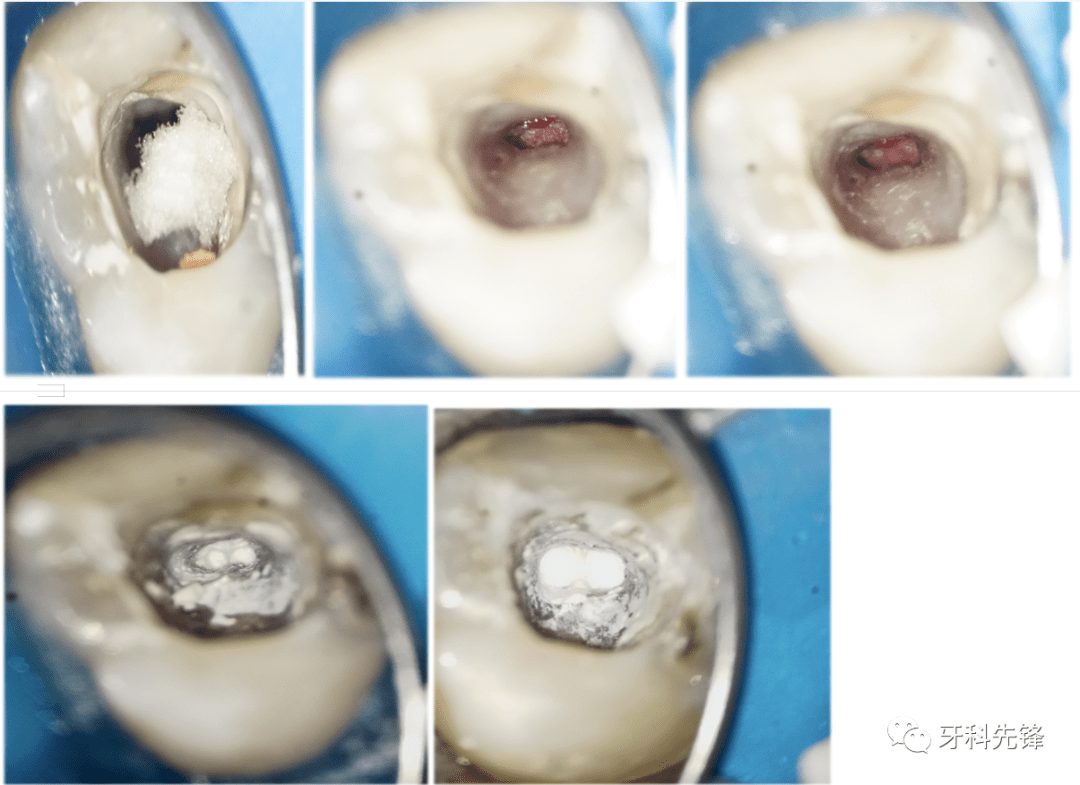

【病例】上(牙合)第二磨牙根尖屏障术一例_治疗_诊断_口腔